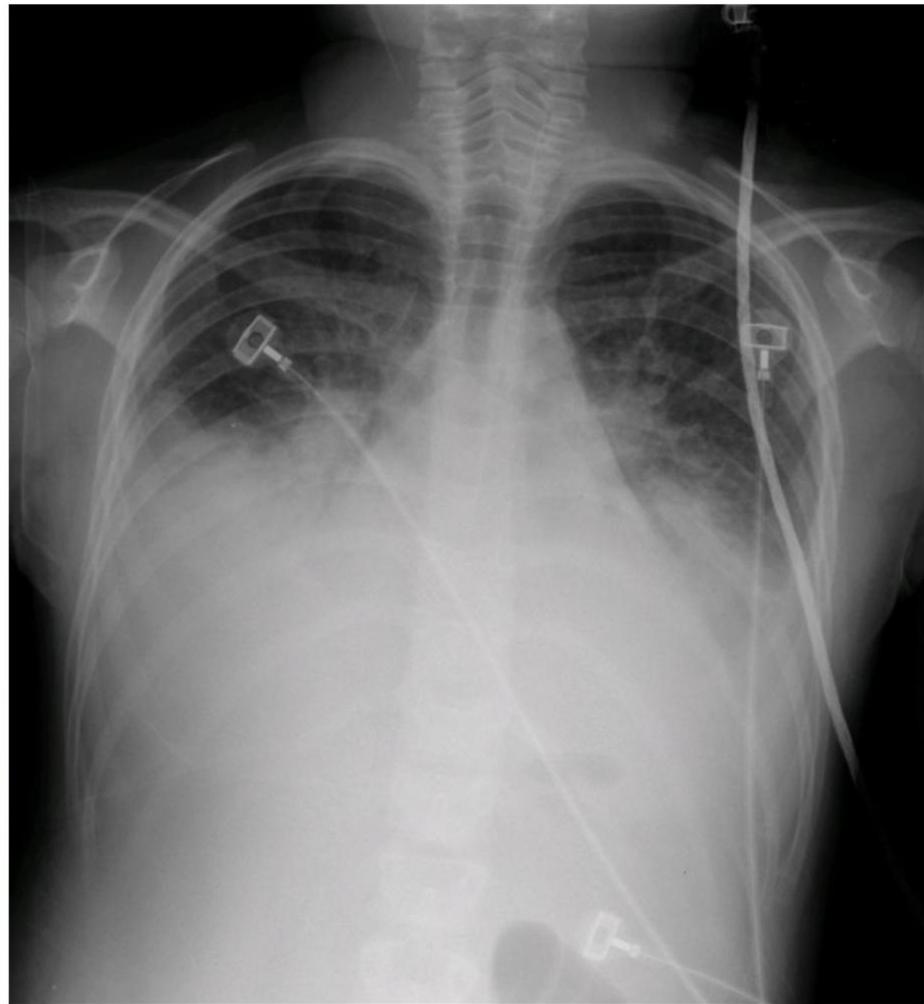

Chest radiograph of a child with fulminant viral myocarditis img-9.jpeg Bilateral lung opacities, sizable bilateral pleural effusions, borderline cardiomegaly. Child was a previously healthy 9-year-old girl who presented with progressive orthopnea, cough, and respiratory distress following 2 weeks of a viral prodrome. Child presented in severe distress and suffered cardiopulmonary arrest shortly after arrival to the emergency department. Management included inotropic support, diuretic therapy, placement of bilateral chest tubes, and intravenous immune globulin. She subsequently made a full recovery.